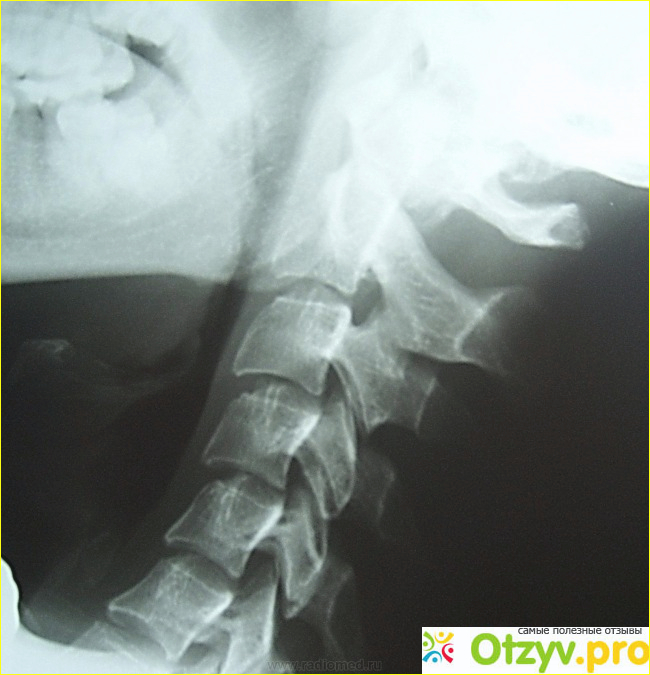

Данное заболевание представляет собой образование в шейном отделе позвоночника каких-то аномальных лишних костных костей (их можно увидеть достаточно четко на фотографии рентгена), которые в свою очередь оказывают давление на артерии находящиеся на шее и тем самым препятствует правильному обращению крови. Когда происходит нарушение давления артериального в головном мозге туда поступает недостаточное количество всех полезных веществ, и конечно это негативно сказывается на его полной функции.